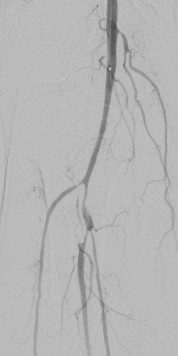

术中DSA:箭头提示双髂动脉血栓栓塞,血流中断

术中DSA:双髂动脉血流恢复